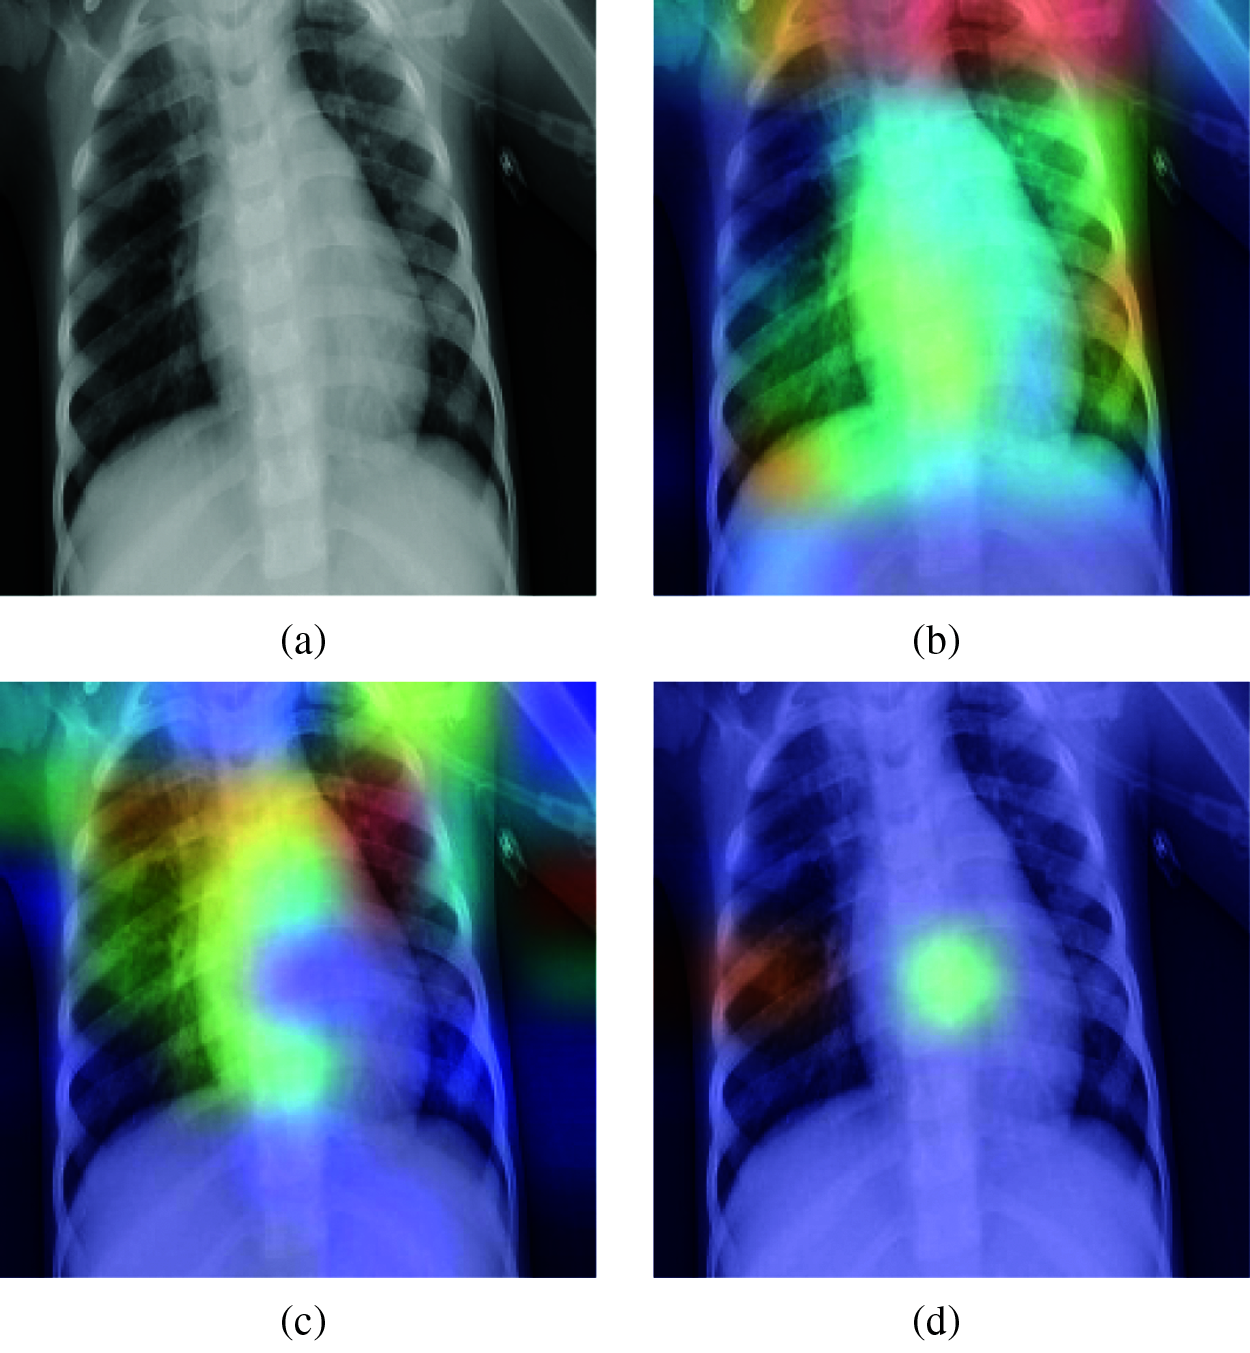

Figure 19: Grad-CAM visualization for predicting a real case of pneumonia: (a) Original case (True class: Pneumonia), (b) VGG-19 (Predicted class: Pneumonia), (c) VGG-16 model (Predicted class: Pneumonia), (d) MobileNetV2 (Predicted class: Pneumonia)

Fig. 19 shows how the different models predicted a pneumonia X-ray image. The results demonstrate that the VGG16, VGG19, and MobileNetV2 models correctly predicted the pneumonia case. Grad-CAM visualization analysis shows that the VGG16 model decision was based on the correct regions of interest in the lungs. The VGG19 model’s Grad-CAM visualization was similar to the VGG16 result with little difference in the region of interest, but it still focused on the correct areas of the lungs. The debugging of the MobileNetV2 model using Grad-CAM visualization showed that the prediction decision was based on a small region in the lungs, which makes the prediction of this model untrustworthy.